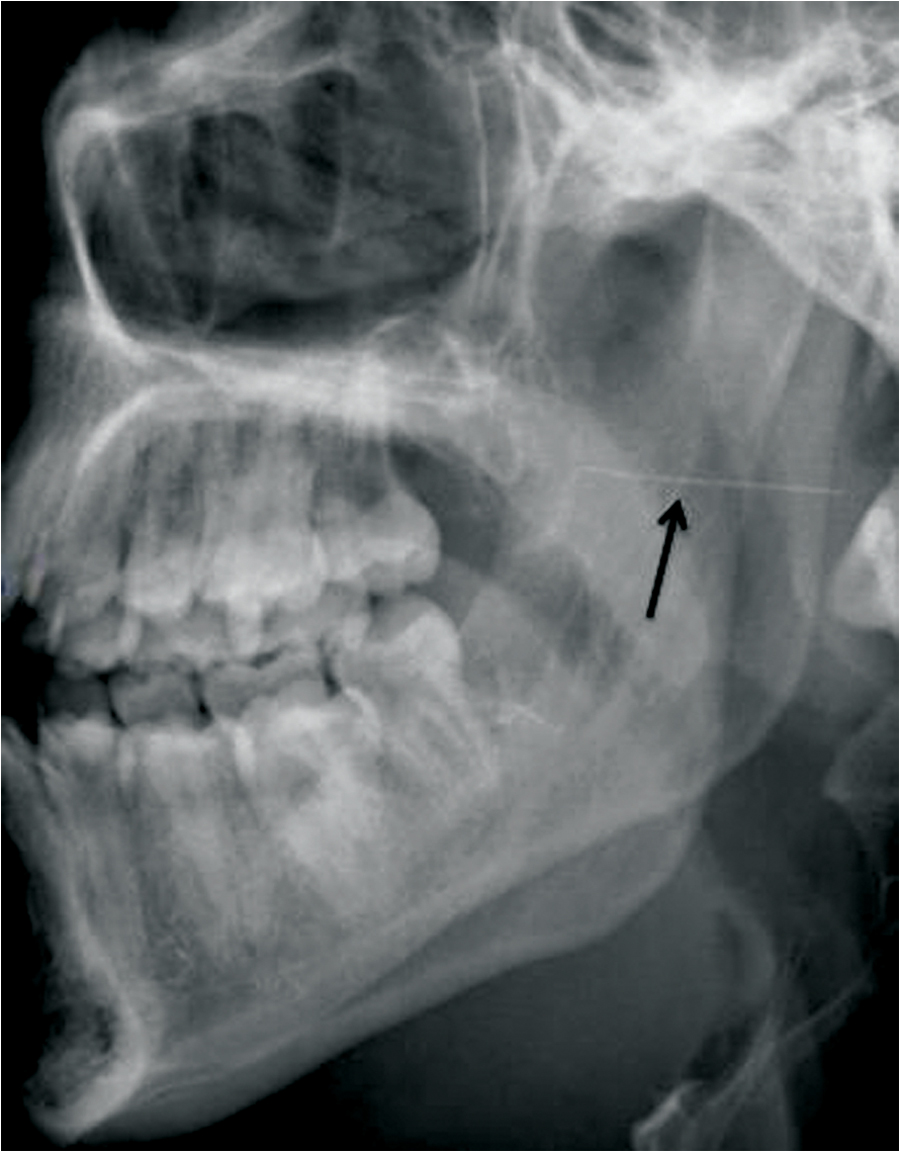

Needle Fracture During Inferior Alveolar Nerve Block: A Case Report of Management Adjacent the Carotid Sheath

Abstract Administration of an inferior alveolar nerve block is a routine technique in clinical practice. Despite mid-century advancements in armamentarium alloy properties, responsible for a significant decline in needle fracture incidence, cases of needle fracture upon local anesthesia administration continue to be reported. Techniques of prevention are paramount. Management of retrieval may pose a challenge … Read more